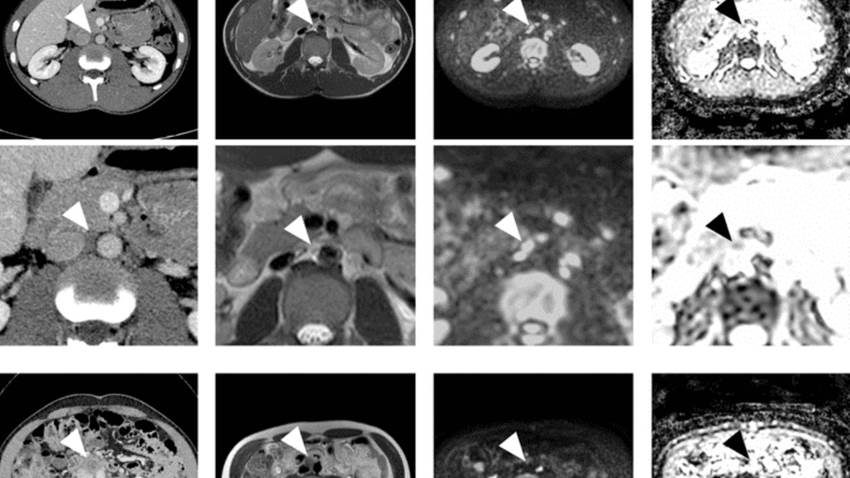

La resonancia magnética reemplazaría a la tomografía computarizada para detectar el Cáncer Testicular

Las preocupaciones sobre la radiación relacionada con las imágenes en pacientes jóvenes con altas tasas de supervivencia han aumentado el uso de imáge...